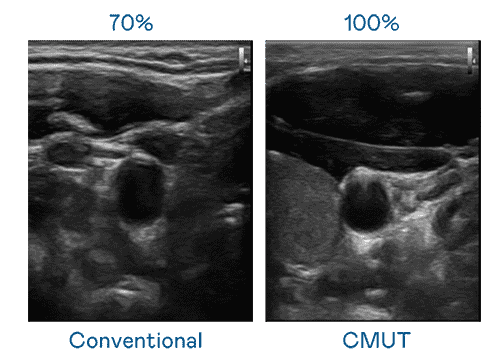

CMUT 技术是一种用电容式微机电元件来产生超音波讯号的技术。。与传统 PZT 压电式技术相比,,,,CMUT 频宽增加 30%,,,,更宽频的超音波讯号让影像解析度大幅提升,,,是实现高影像品质医疗超音波扫描、、、、促进精准医疗发展的关键技术。。。。

大频宽带来超清晰影像

超音波影像的解析度高低,,,,首先取决于探头能发出的讯号频宽。。。。尊龙z6 CMUT 可提供高清晰的超音波讯号,,,,提供高频宽、、、高灵敏度、、、影像纹理细节更高的超音波影像,,协助医护人员缩短影像判读时间及利用精准的医疗影像进行诊断。。。。